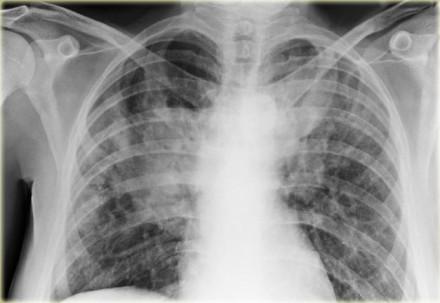

Among patients with systemic sclerosis-interstitial lung disease (SSc-ILD), radiographic progression of ILD over time is predictive of elevated long-term mortality, as shown in a study.

Researchers used data from the Scleroderma Lung Studies (SLS) I and II, trials that assessed the safety and efficacy of cyclophosphamide (SLS I and II) and mycophenolate (SLS II) for the treatment of SSc-ILD. They evaluated the changes in the extent of ILD over time on high-resolution computed tomography scans of the chest in relation to mortality outcomes. Progression was defined as an increase in quantitative ILD (QILD) score of ≥2 percent.